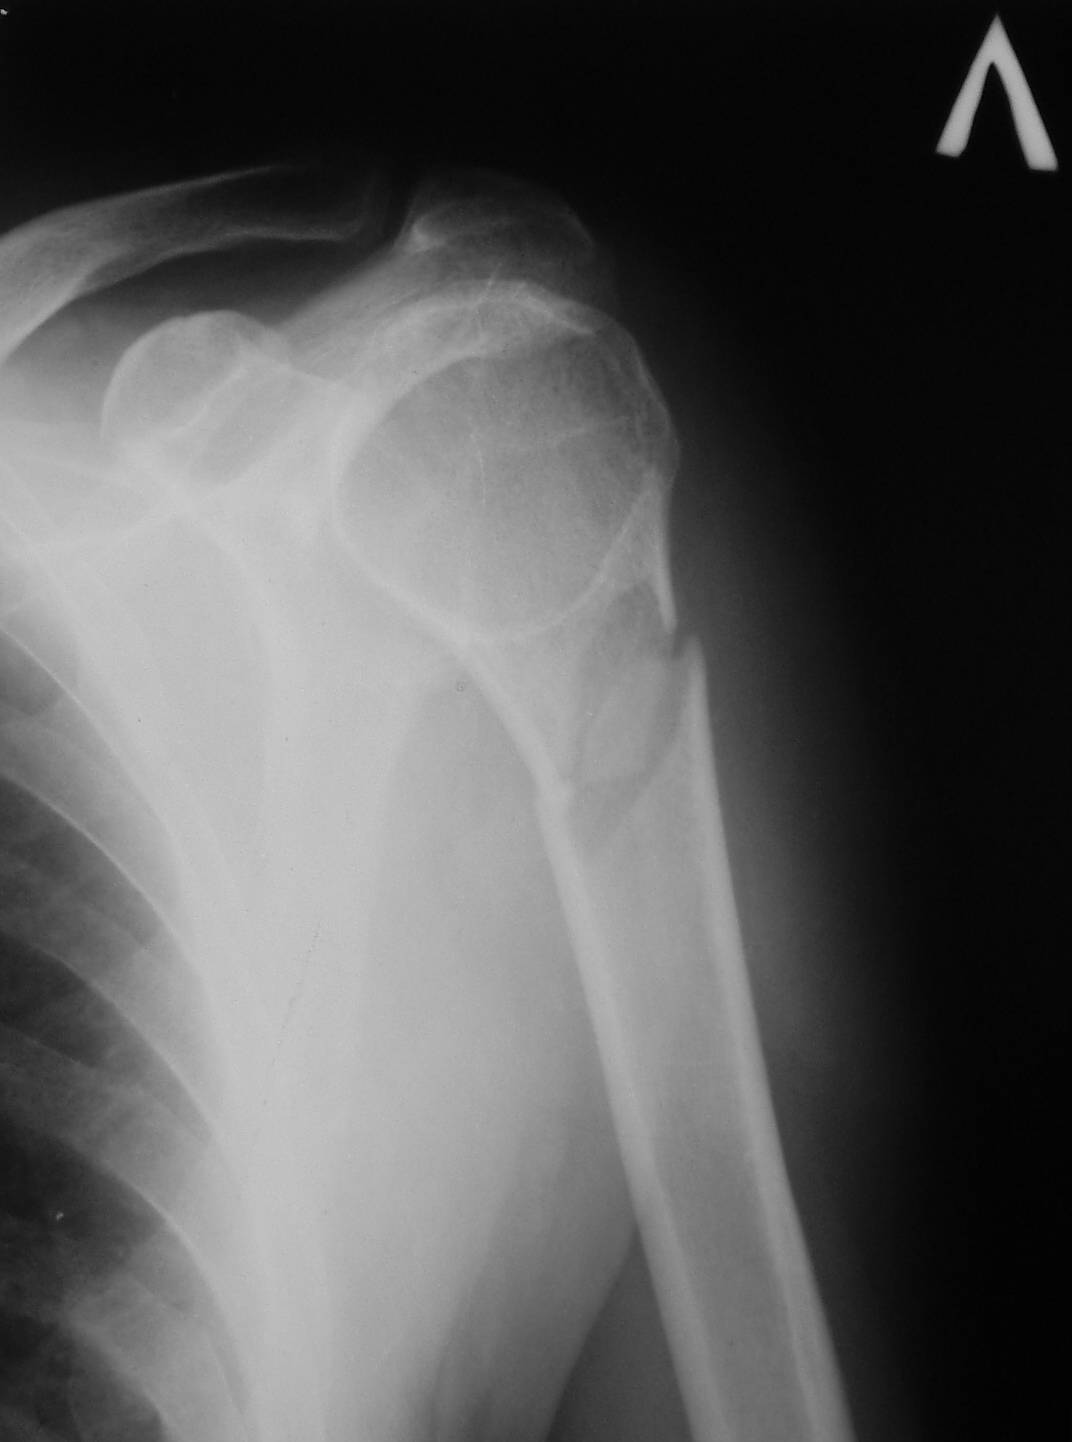

Уважаемые коллеги! Помогите советом. Мужчина 69 лет, вчера упал на

скользкой дороге.

Рентгенологически патологический перелом шейки левой плечевой кости,

наличие секвестра, шаровидная полость в головке. До травмы - жалоб

небыло. При осмотре отек не выражен. Что бы вы сделали для уточнения

диагноза?

Имя     : Absces Brody.JPG